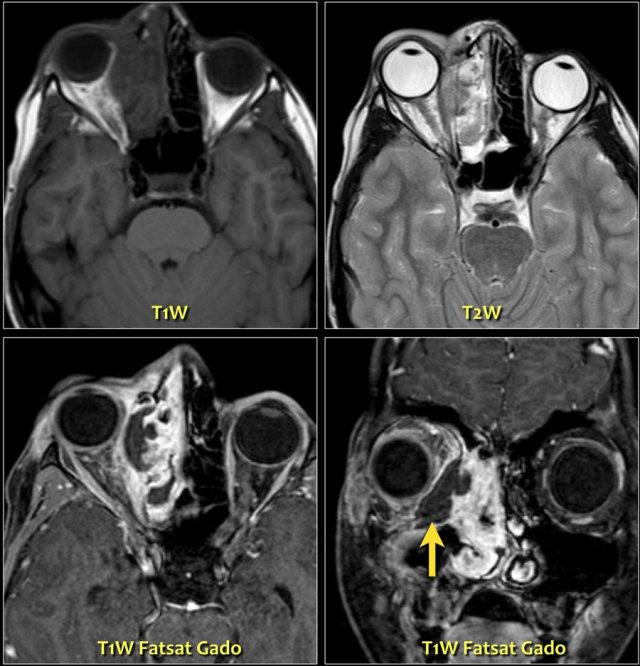

Hội chứng Devic

Hội chứng Devic còn được gọi là viêm tủy thị thần kinh (neuromyelitis optica).

Hãy quan sát hình ảnh trước, sau đó chúng ta sẽ thảo luận chi tiết hơn.

Trên hình bên trái, thần kinh thị giác bên phải có hình ảnh bình thường.

Lưu ý rằng thần kinh thị giác là một bó chất trắng.

Nó có cùng cường độ tín hiệu với chất trắng trong não.

Ở phía đối bên, thần kinh thị giác có tín hiệu tăng cao.

Đây là tổn thương ngoài nhãn cầu trong nón cơ, và chúng ta cần nghĩ đến các bệnh lý tân sinh so với bệnh lý mất myelin.

Tiếp tục xem hình ảnh tiếp theo.Bên trái là hình ảnh chuỗi xung FLAIR kết hợp kỹ thuật ức chế mỡ (fat-sat).

Lưu ý tín hiệu bất thường và thực tế là thần kinh thị giác không bị phì đại, điều này giúp loại trừ khả năng u.Hình ảnh tủy sống cổ cho thấy một đoạn dài tổn thương không chiếm chỗ.

Dựa trên các hình ảnh này, chẩn đoán phân biệt bao gồm xơ cứng rải rác (MS) và hội chứng Devic (còn gọi là viêm tủy thị thần kinh).

Do MS phổ biến hơn nhiều, đây sẽ là chẩn đoán có khả năng nhất, nhưng trường hợp này thực tế là hội chứng Devic.Một số tác giả coi hội chứng Devic là một thể của MS, tuy nhiên hội chứng Devic khác với MS ở các điểm sau:

- Bệnh nhân có tình trạng rất nặng, do hội chứng Devic có diễn tiến cấp tính và ác tính hơn.

- Thường có sự kết hợp giữa mù một mắt và liệt hai chi dưới do tổn thương viêm tủy cắt ngang đoạn dài (trong MS thường chỉ một hoặc hai đoạn).

- Hội chứng Devic thường có diễn tiến đơn pha.

- Thường không có mảng xơ cứng ở não.

Xơ cứng rải rác (MS)

Bên trái là hình ảnh của một bệnh nhân khác, cũng có viêm thần kinh thị giác.

Có tín hiệu tăng trong thần kinh thị giác và trong não có nhiều tổn thương là hậu quả của MS.

Các tổn thương này không xuất hiện cùng một thời điểm, do đó có sự phân tán theo thời gian và không gian, đây là đặc điểm đặc trưng của MS.-

50% bệnh nhân viêm thần kinh thị giác cuối cùng sẽ tiến triển thành MS.

50% còn lại có viêm thần kinh thị giác đơn độc (xem chẩn đoán phân biệt ở trên). - 80% bệnh nhân MS sẽ có biểu hiện viêm thần kinh thị giác tại một thời điểm nào đó trong quá trình bệnh.